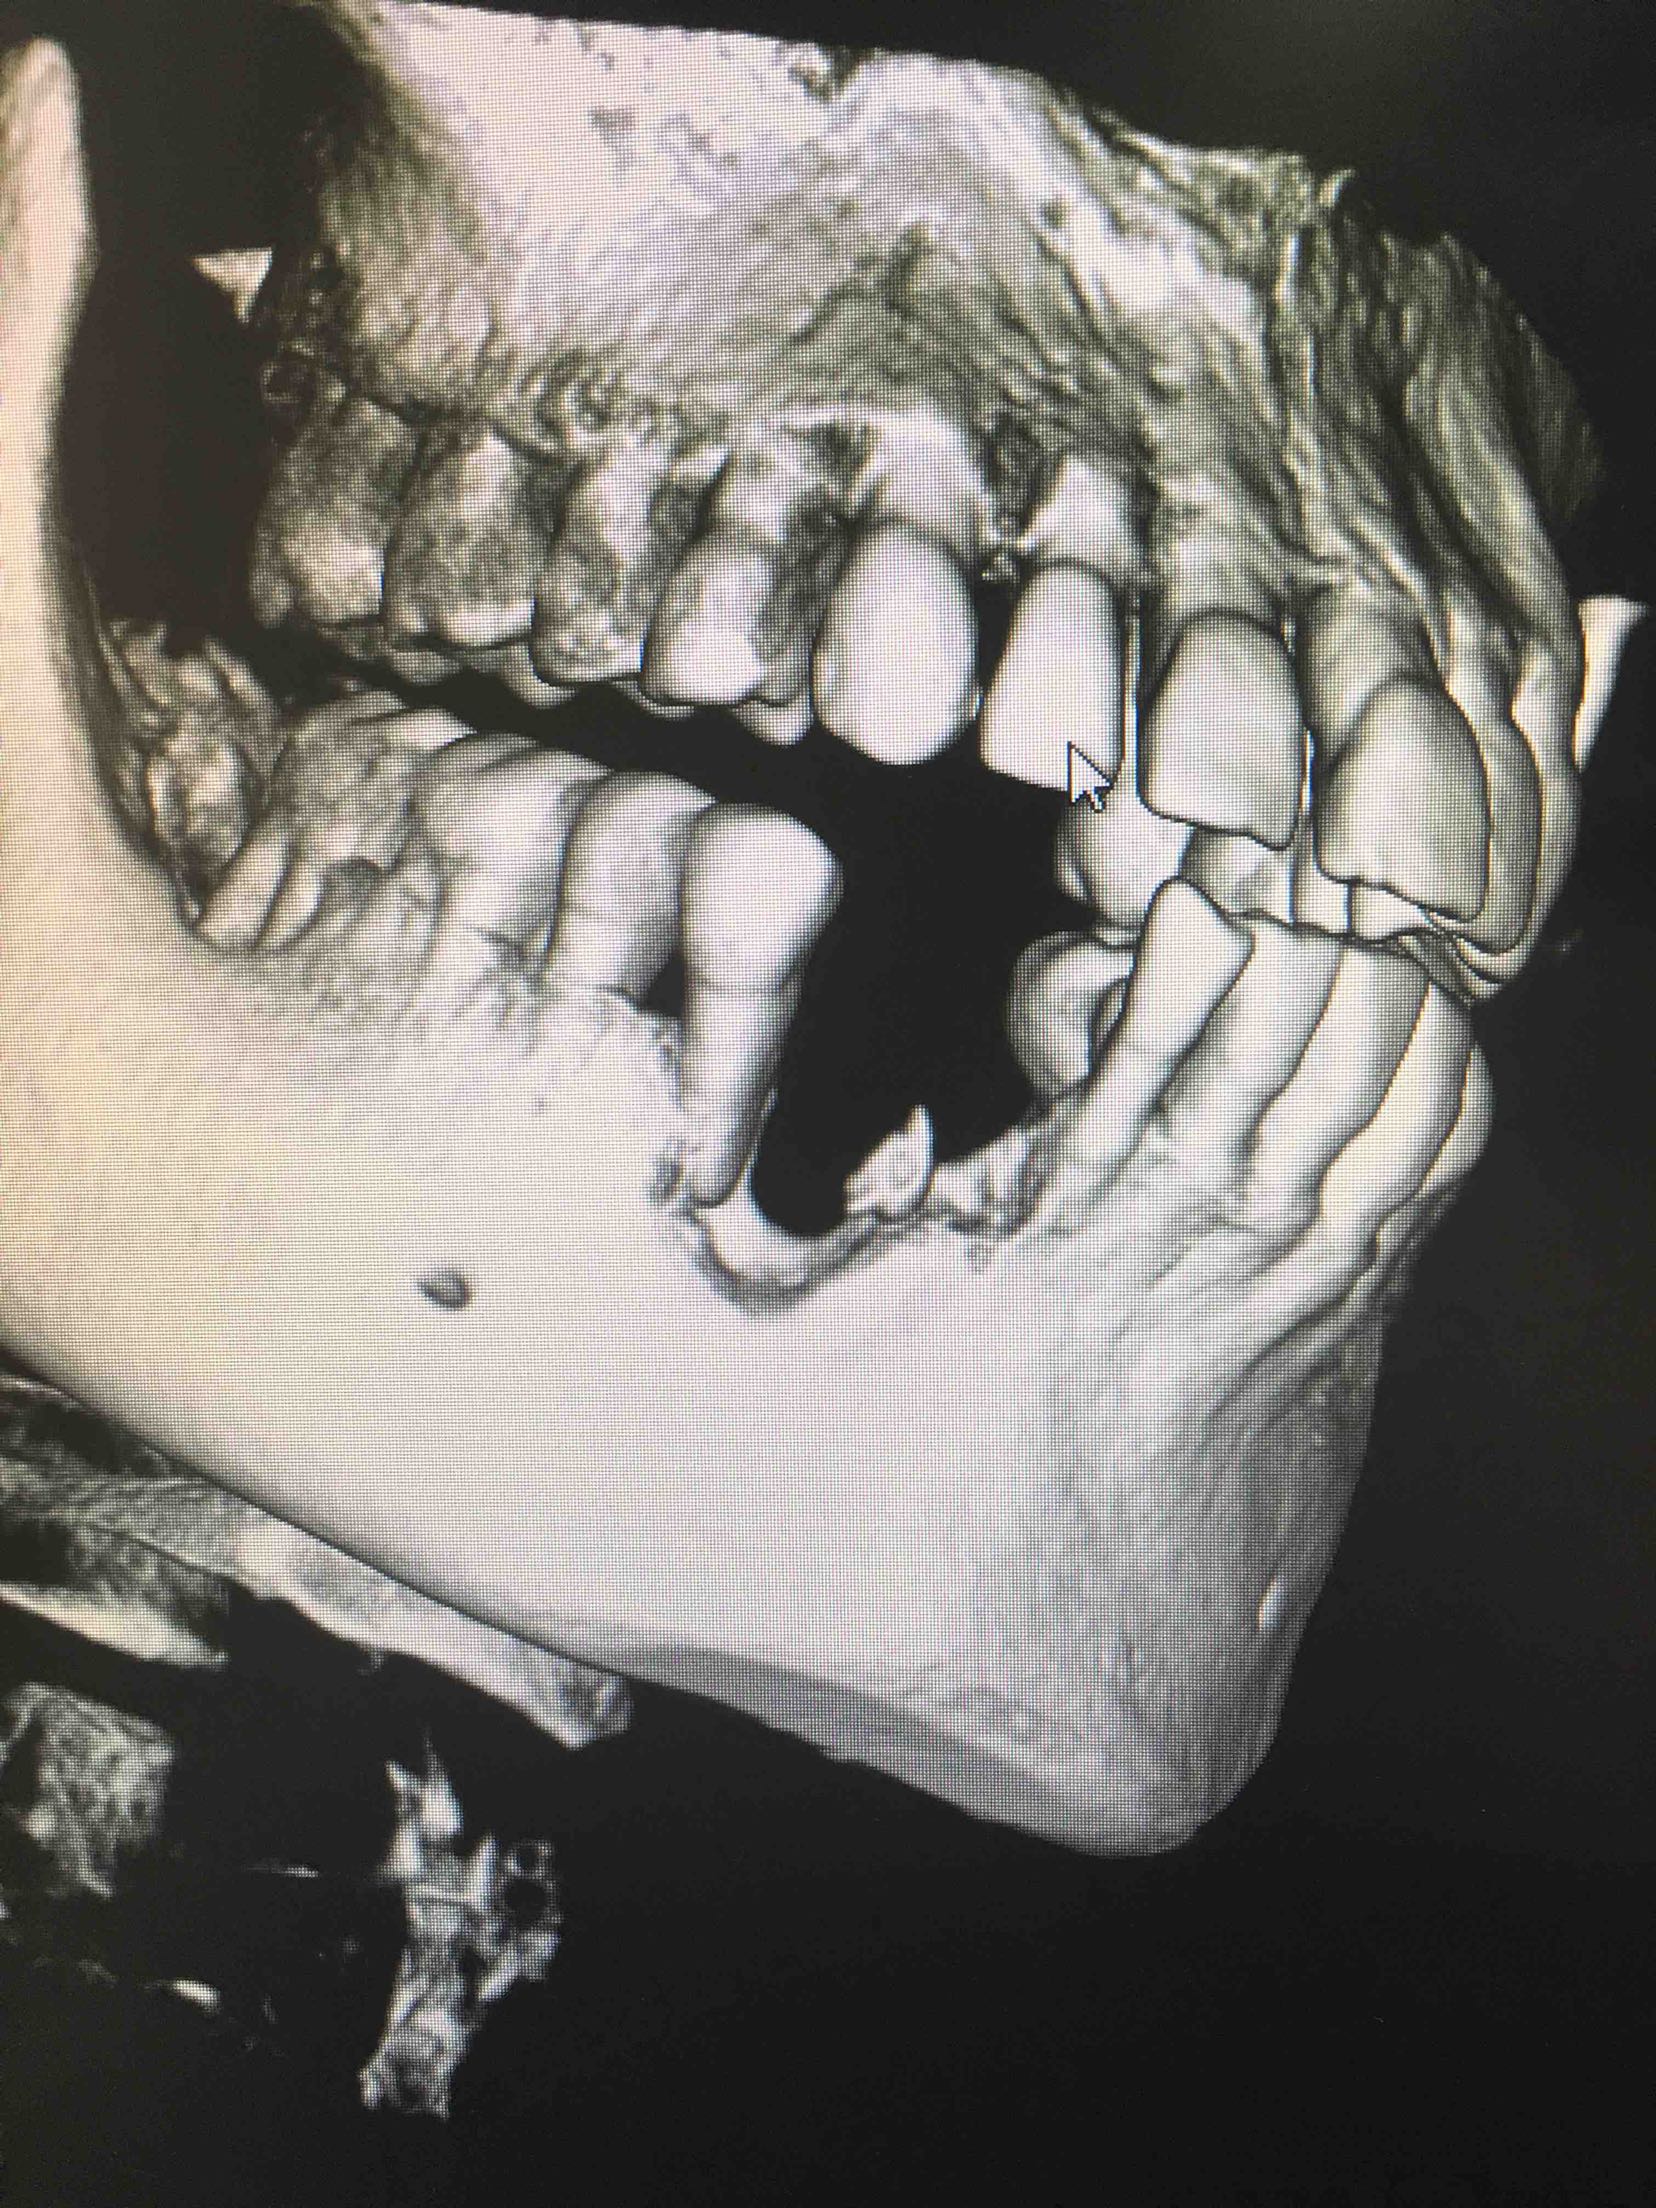

两周后,局麻下,翻瓣拔除44牙,在41、42根方环形钻取骨块,钛钉固定于43牙骨缺损处,Bio-ss骨粉0.25g,海奥生物膜,严密缝合!嘱半年后植牙!

植入42、44登腾3.4-10两枚植体

三个月后,牙龈成型前,口内照,未完待续……